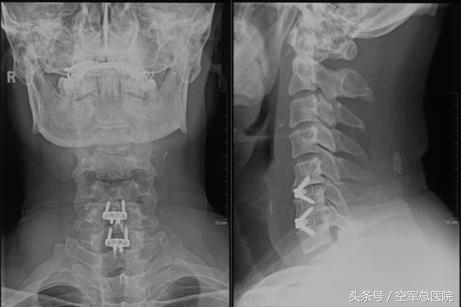

结合影像资料和患者职业特点,医生认为,保守治疗恐怕已经不能解决患者问题,手术治疗应该是最佳选择。杜主任带领科室人员对患者病情反复进行讨论,经慎重考虑,决定由他带领陈宇飞、张振宇、刘悦及许砾思医生为患者实施“前路颈5-7椎间盘切除减压、植骨融合内固定术”。手术从患者颈前右侧沿皮纹切开一个4cm的切口,在切除颈5-6,颈6-7退变椎间盘的同时,用超声骨刀切除颈6-7左侧增生的钩椎关节并扩大左侧的神经根孔。随着一个个“老茧”的剔除,患者神经压迫症状迅速得到缓解,达到了美观、微创的效果(见下图)。手术历时约2小时,出血量极其微少约2毫升左右。

术后,患者左手麻木疼痛及灵活性下降等症状消失,术后第2天,患者独立下地行走无任何不适,术后5天患者平安出院,佩戴颈围继续他的演出生涯。“手不麻了,弹奏乐器的感觉一下子恢复到最佳状态。”患者激动地表示。